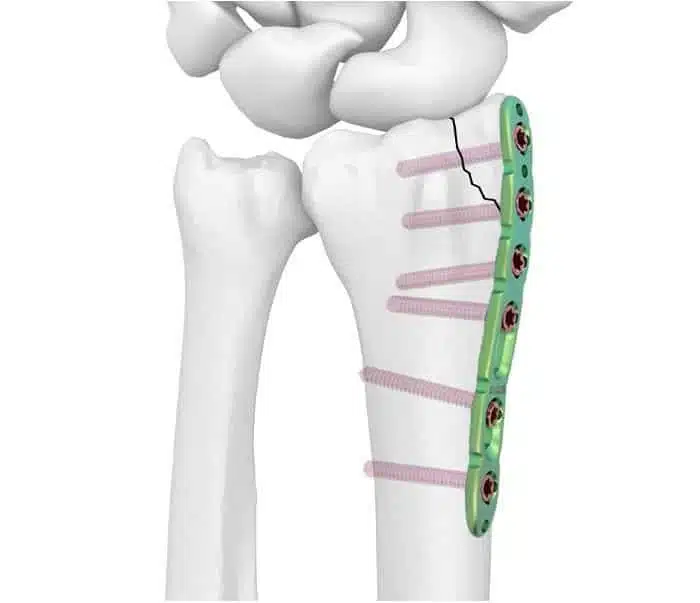

المسمار النخاعي هو عبارة عن جهاز أو قطعة مصنوعة من مكادة معينة مثل التياتنيوم تكون بشكل طولي يشبه المسمار وفي نفس الوقت يشبه العظمة التي سيكون بديل لها.

ويوجد عدة أنواع من المسامير مثل مسامير الخاصة بقصبة الساق، ومسامير خاصة بالفخذ، وهذا يعني أن هذا النوع من العلاجات يركز على المشكلات التي تتعرض لها الساق.

- كسر العظام: يتعرض العديد من الأشخاص للكسر في العظام ويتم اللجوء إلى مسمار النخاع في الحالات الشديدة من الكسر، حيث تستخدم لتثبيت العظام المكسورة والتي على شكل طولي.

- يعتبر البديل الأمثل للشرائح والمسامير حيث لا تحتاج إلى جراحة كبيرة.

يمكن أن يتم إجراء عملية تركيب مسمار نخاعي بالساق حتى تعطي ثبات أكبر للجزء المصاب ويعمل المسمار على تحمل جزء من الوزن الموضوع على الساق مما يعطي فرصة لالتئام الجرح والوصول إلى مرحلة التعافي السريع، ويعطي ثبات أفضل للساق، كما أنه لا يؤثر على الحركة أو سريان الدورة الدموية في الجسم.

خلال عملية تركيب المسمار النخاعي في الساق بعد الكسر يبدأ الطبيب في تثبيت المسمار في الساق لكي يصل بين طرفي الكسر ويعطي إمكانية لالتئام الكسر والشفاء أسرع ويتمكن المصاب من الرجوع إلى نشاطه البدني بعد فترة النقاهة.